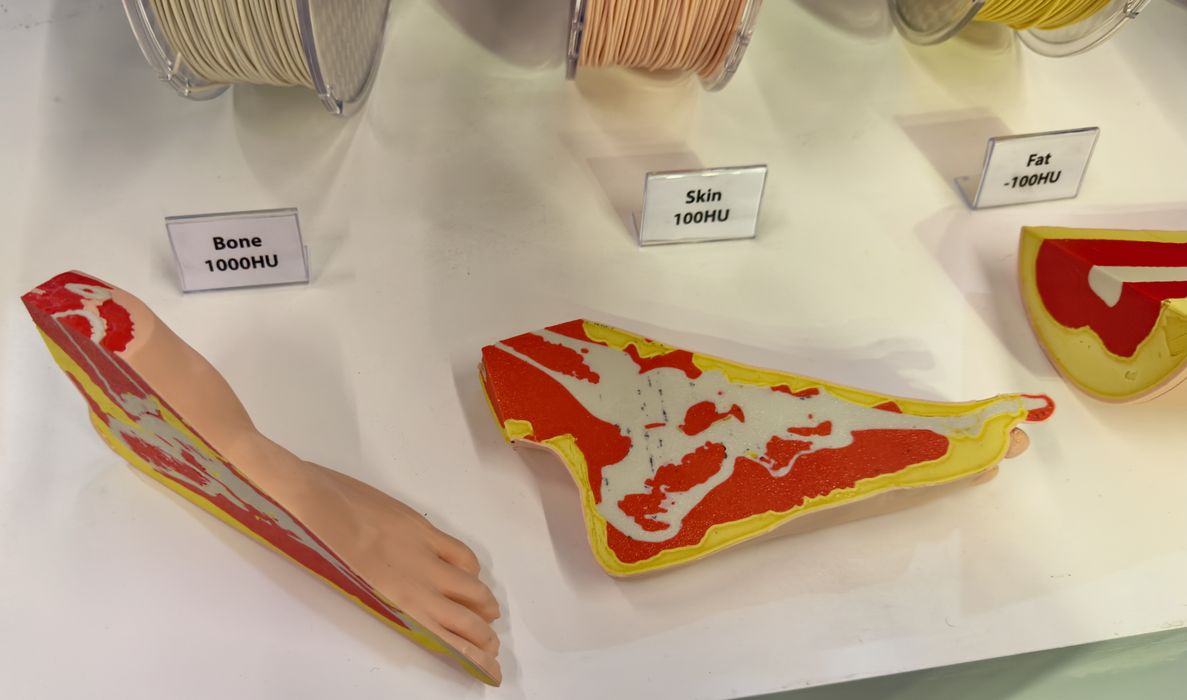

Lugo Labs Develops 3D Printing Filaments Mimicking the Human Body

Korean company Lugo Labs has developed a very unusual set of materials for the medical industry.